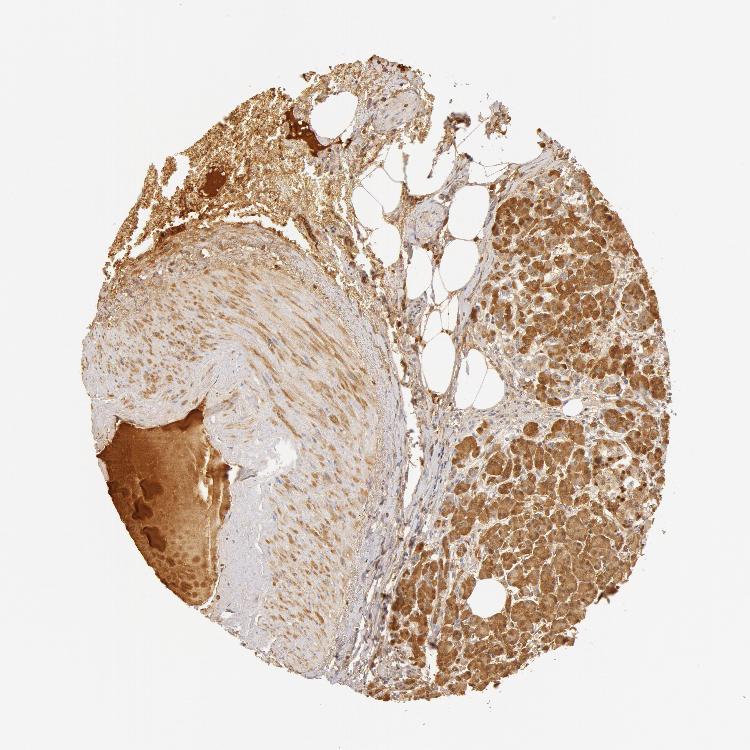

PANCREAS - Antibody stainingi

Antibody staining in the annotated cell types in the current human tissue is reported as not detected, low, medium, or high, based on conventional immunohistochemistry profiling in selected tissues. This score is based on the combination of the staining intensity and fraction of stained cells.

Each image is clickable and will lead to virtual microscopy that enables deeper exploration of all samples and also displays staining intensity scores, fraction scores and subcellular localization as well as patient and tissue information for each sample.

Antibody HPA001524Antibody HPA001525Antibody CAB026209

Exocrine glandular cells Not detectedNot detectedNot detected

Pancreatic endocrine cells Not detectedNot detectedNot detected